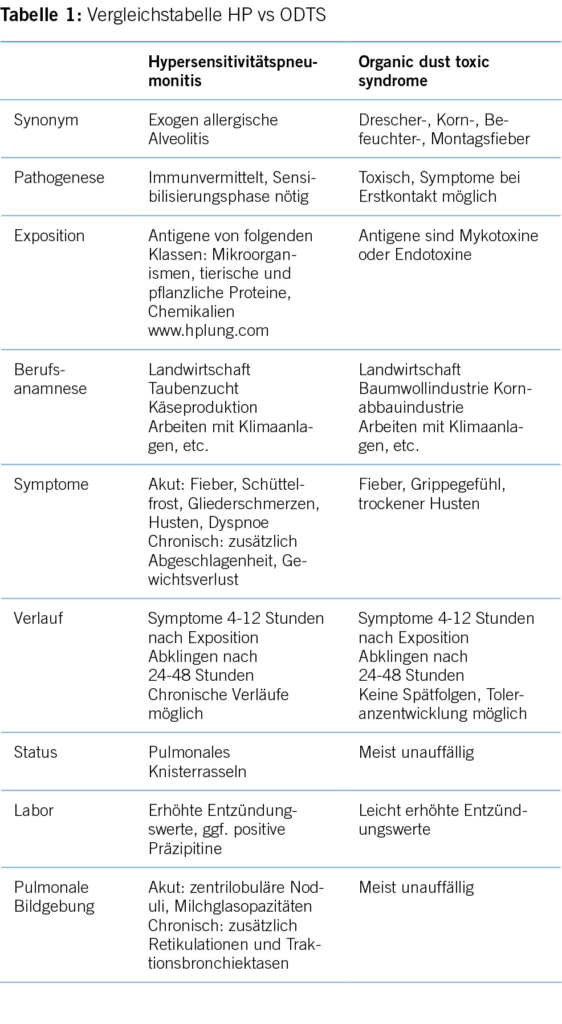

Bereits 1992 gab es Diskussionen bezüglich des Begriffs «Inhalationsfieber» [2], allerdings wurde bis heute kein Konsens bezüglich einheitlicher Nomenklatur gefunden. Gemäss Hendrick et al. werden unter dem Begriff «Inhalationsfieber» [3] eine Gruppe von grippeartigen Syndromen wie z.B. das Metalldampffieber, das Polymerrauchfieber und das organic dust toxic syndrom (ODTS) zusammengefasst. Die Hypersensitivitätspneumonitis (HP), traditionell auch exogen allergische Alveolitis (EAA) genannt [4], welche immunbedingt ebenfalls zu Fieber führt und oft ihren Trigger in der Arbeitswelt findet, wird in der Literatur nicht unter dem Begriff der «Inhalationsfieber» subsumiert.

Durch die Inhalation von organischen Stäuben können die Krankheitsbilder der Hypersensitivitätspneumonitis (HP) und des organic dust toxic syndromes (ODTS) entstehen. Anorganische Substanzen, z.B. in Form von Dampf oder Rauch, verursachen u.a. das Metalldampffieber.

Da für die Krankheitsauslösung eine Sensibilisierungsphase benötigt wird, gibt es kein Auftreten nach einem Erstkontakt. Ob die Krankheit schliesslich ausbricht, ist abhängig von der Dauer der Exposition, der Staubkonzentration und der genetischen Prädisposition des Patienten [4].

Unterschieden wird eine akute, subakute und chronische Form der HP [11]. Die akute Form äussert sich mit Fieber, Schüttelfrost, Gliederschmerzen und pulmonaler Symptomatik (Husten und Dyspnoe) vier bis zwölf Stunden nach massiver Antigenexposition (Bsp. Reinigung eines Taubenschlages) und klingt nach 24 bis 48 Stunden spontan wieder ab. Oft heilt eine akute Form ohne Spätschäden aus. Hingegen braucht es für die chronische Form der HP Kontakt mit kleineren Antigenmengen über einen längeren Zeitraum. Die Symptome sind dann unspezifischer; es zeigen sich trockener Husten, Abgeschlagenheit, Gewichtsverlust und sind assoziiert mit einer schlechteren Prognose.

In der klinischen Untersuchung findet man beim Vorliegen einer bereits fibrotischen (respektive chronischen) Manifestation zumeist ein Knisterrasseln (Sklerosiphonie, velcro rales). Lungenfunktionell zeigt sich eine Restriktion. Eine Diffusionsstörung mit Abfall der Sauerstoffsättigung unter Belastung sind typisch bei fortgeschrittener Erkrankung.

Erhöhte Entzündungsparameter (Leukozyten, CRP) und teils positive antigen-spezifische Immunglobuline G Werte (Präzipitine) sind in der laborchemischen Untersuchung zu detektieren. Durch positive, spezifische IgG kann die Diagnose nicht bestätigt werden, ebenso wenig können negative IgG die Krankheit ausschliessen [10].

Richtungsweisend ist sicherlich die radiologische Bildgebung (HRCT) mit den typischen Befunden der Akutphase wie zentrilobuläre Noduli, Milchglasopazitäten, Airtrapping in Exspiration und in der chronischen Phase zusätzlich Retikulationen und Traktionsbronchiektasen [7].

Als Differentialdiagnose zur HP ist das organic dust toxic syndrome (ODTS) [13] zu nennen. Hierbei handelt es sich um eine toxische Alveolitis, welche vier bis zwölf Stunden nach Inhalation von organischem Staub auftritt. Antigene sind dabei Mykotoxine oder Endotoxine, herkommend von u.a. schimmligem Getreide, Heu, Zellwandbestandteile von gramnegativen Bakterien und Pilzsporen. Folgedessen sind Arbeitsumgebungen in der Landwirtschaft (speziell Geflügel- und Schweinezucht), aber auch beispielsweise Baumwoll- oder Kornabbauindustrie [3] und Arbeiten mit/bei (schimmligen) Klimaanlagen/Befeuchtungssystemen betroffen. Klinische Erkrankungen sind u.a. das Drescher-, Korn- und Befeuchterfieber und das Siloentladesyndrom, welche alle deutlich häufiger in den Sommermonaten auftreten [3].

Bei regelmässigem Kontakt mit der auslösenden Substanz kann es einerseits zu einer Toleranzentwicklung beim ODTS kommen, andererseits klingen die Symptome nach 24 bis 48 Stunden spontan wieder ab und Spätfolgen werden nicht gesehen. Aufgrund der genannten Toleranzentwicklung kommt es typischerweise am Montag nach einem arbeitsfreien Wochenende/Urlaub wieder zu Beschwerden (sogenanntes «Montagsfieber»). Oft tritt ein ODTS auf, nachdem eine grosse Antigenmenge freigesetzt wurde, dies in Folge z.B. einer Siloreinigung, einer Be-/Entladung grosser Heumengen oder einer Kompostleerung. Die Krankheit tritt mit einer Inzidenz von 20-190/10000 häufiger als die HP auf. Wie es der Name sagt, handelt es sich um eine toxisch ausgelöste Erkrankung, d.h. liegt die Staub Exposition über einem gewissen Schwellenwert, erleiden ganze Menschengruppen, sogenannte Cluster, ähnliche Symptome [14]. Eine Sensibilisierung ist nicht nötig und Beschwerden können bereits bei der ersten Exposition auftreten. Interessanterweise sind sowohl bei der HP als auch beim ODTS mehr Nichtraucher als Raucher betroffen [12, 15].

Die Patienten klagen über einen trockenen Husten und ein akutes, febriles Krankheitsgefühl (inklusive Myalgien, Kopfschmerzen). In der laborchemischen Untersuchung zeigt sich eine milde Leukozytose. Im Gegensatz zur HP sind der Auskultationsbefund und die radiologische Bildgebung zumeist unauffällig und in der bronchoalveolären Lavage (BAL) finden sich vorherrschend Neutrophile.